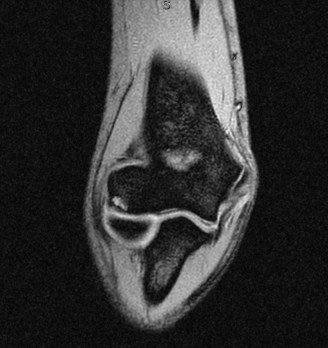

On examination, he has tenderness to palpation over his olecranon and pain with terminal elbow extension. He has no evidence of varus or valgus instability. No pain with resisted wrist flexion. His images are shown (Figs. 2–108 to 2–110).

Figure 2–108